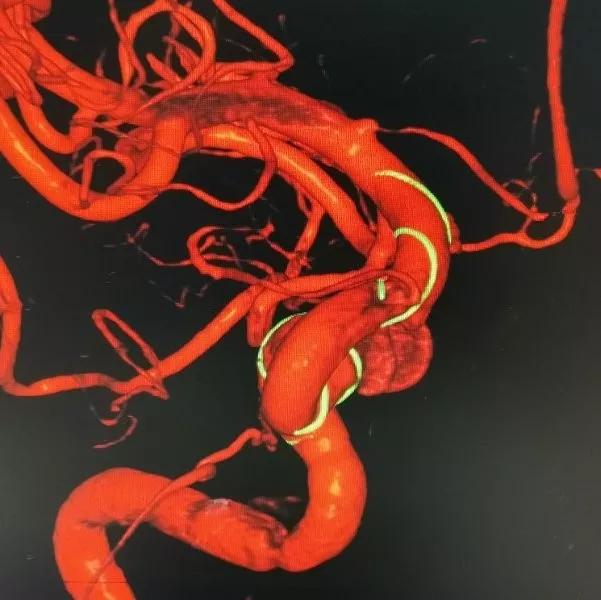

再行右侧颈内动脉血流导向装置置入术:将8F Envoy导引导管置入右侧颈总动脉,105cm 6F Navien导引导管头端置入颈内动脉岩骨段,造影见海绵窦段3个动脉瘤,由近及远直径一次为5mm、8mm、9mm,颈内动脉床突上段可见一大小约为5×4mm的宽颈动脉瘤。

3D重建图像